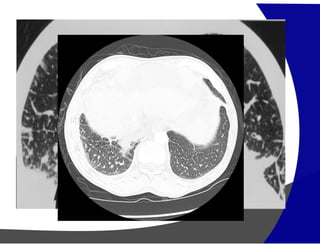

Opacidades em Vidro Fosco

(Pneumonia Descamativa Intersticial)

(Pneumonia por Pneumocystis carinii)

Opacidades em VidroFosco (Pneumonia Descamativa Intersticial)

Opacidades em VidroFosco (Pneumonia por Pneumocystis carinii)